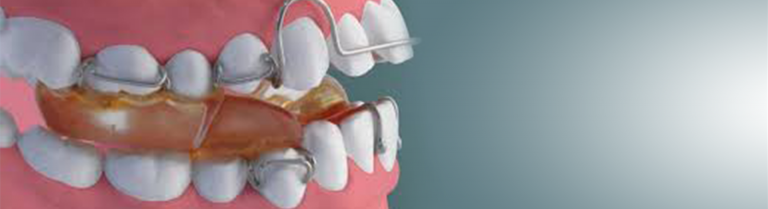

מכשיר לקידום לסת תחתונה

מכשיר פונקציונלי שנועד למקם את הלסת התחתונה במיקום שונה ממה שהיא נמצאת וכך לתקן עמדה אחורית, אסימטריות וכדומה.